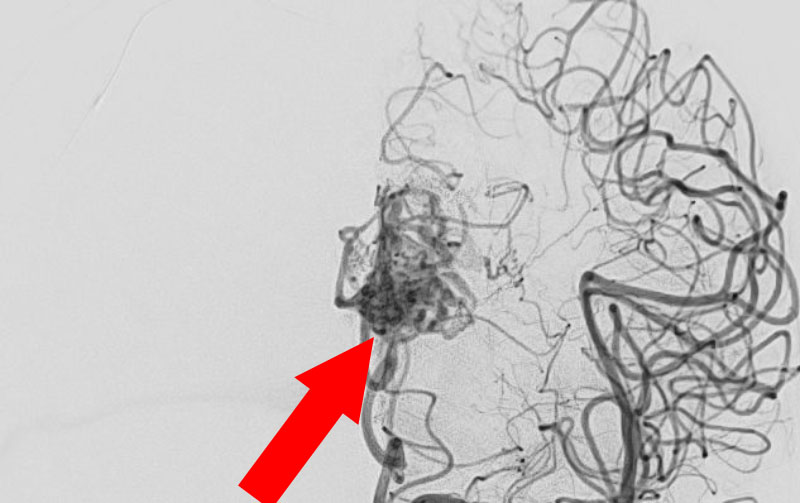

No.1585 手術前

No.1585 手術中

No.1585 手術後